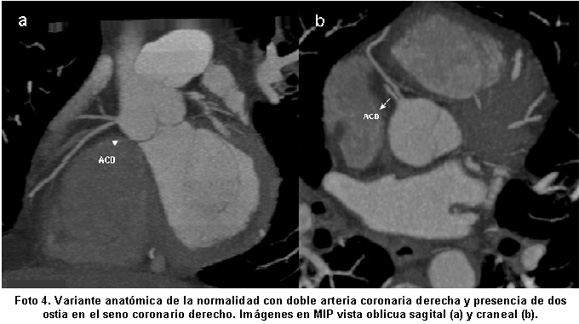

Las anomalías anatómicas más comunes en este estudio fueron la duplicación o triplicación de vasos coronarios con una frecuencia de 23% (Fotos 3 y 4) y ausencia de tronco izquierdo (15%), que no tienen interés clínico. De las anomalías con importancia clínica más frecuentes fueron la ACD con origen en el seno de Valsalva izquierdo y trayecto interarterial (15% Fotos 5 y 6), discurriendo entre la aorta y el tronco de la arteria pulmonar, patrón que se puede asociar con alto riesgo de isquemia inducida por ejercicio y muerte cardíaca súbita6. Otras anomalías son el origen aberrante de la ACX desde el seno de Valsalva derecho con o sin trayecto interarterial (15% casos. Foto 7) y el puente intramiocárdico (11%. Foto 8).